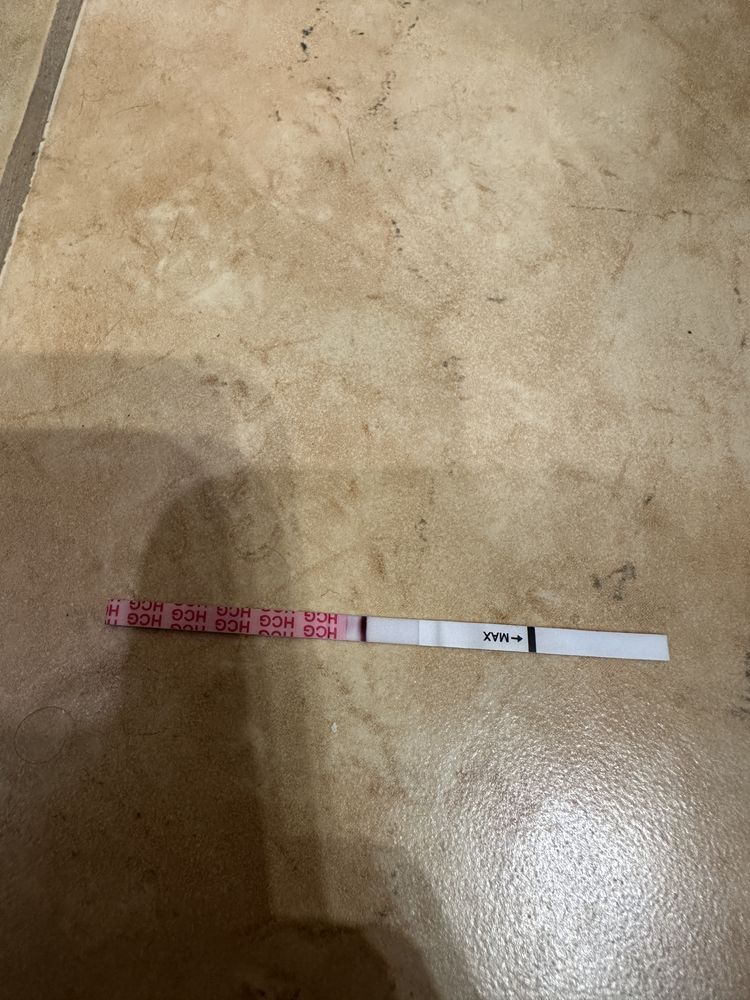

Овуляция была или ещё будет?

Как думаете, овуляция была уже? Если да, то на какой дц?

1 февраля тест положительный,значит была 1-3 февраля

Наталья, а почему тогда не снижается ЛГ, не знаете? На сколько я знаю, то должно снижаться.. вот Фемометр мне показывает сегодня пик🫠

Elena Krushelnytskaya, а от 1 числа что фемометр говорит?там самый яркий тест

Наталья, от первого тоже говорил пик, и тоже 200%🤔

я ради интереса несколько циклов после родов делала тесты на овуляцию, то после пика тесты тускнели.

Наталья, поэтому я и думаю что странный цикл, странные тесты, графики - не перерос ли фоликул в кисту. А то такое ощущение, что овуляция вот-вот наступит и не наступает (по тестах и графику). А вот симптомы все второй фазы (выделения, боль в груди, аппетит, усталость, головная боль)

про лг вот читала, поэтому такое ощущение, что фолликул перерос в кисту🥺

раньше на 17-19 дц ловила пик

Elena Krushelnytskaya, может вторая овуляция?но полоска не такая яркая,как 1 февраля.Остается два варианта - или к врачу на прием или ждать монстриков и тогда все понятно будет

Если у женщины исходно повышен уровень ЛГ, тест может оказаться положительным. Такая ситуация наблюдается у пациенток с преждевременной недостаточностью яичников, а также в позднем репродуктивном возрасте, когда уровни гонадотропинов (ФСГ и ЛГ) изначально повышены.

Бывают ситуации, когда повышение уровня ЛГ начинается, но оказывается недостаточным. Овуляции не происходит, а преовуляторный фолликул преобразуется в фолликулярную кисту.